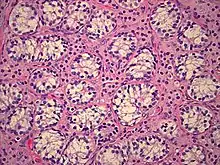

| AIS results when the function of the androgen receptor (AR) is impaired. The AR protein (pictured) mediates the effects of androgens in the human body. | |